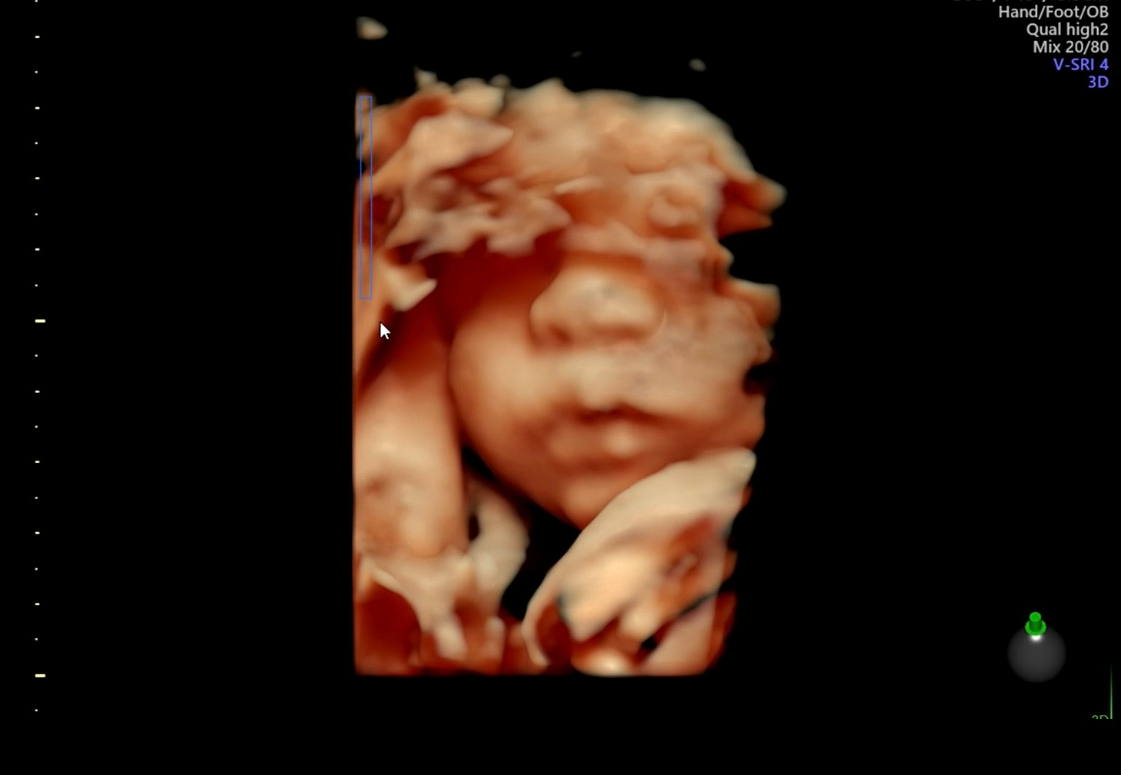

우리 아이 정밀초음파 사진 기록 임신 기간 중 가장 긴장되고도 중요한 검사 중 하나가 바로 정밀초음파 검사였어요.

아이 얼굴을 보는 설렘도 있지만, 머리부터 심장, 팔다리, 장기까지 하나하나 꼼꼼히 확인하는 검사라 검사 전에는 괜히 마음이 조급해지더라고요.

✔️ 머리와 얼굴 구조

✔️ 심장 박동 및 구조

✔️ 척추와 팔다리

✔️ 장기 발달 상태

등을 하나하나 설명해주셔서 현재 주수에 맞게 잘 자라고 있다는 걸 확인할 수 있었어요.

정밀초음파 사진을 받아보니 괜히 더 조심스럽게 보게 되더라고요.

사진도 여러 각도로 남겨주셔서